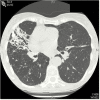

Nontuberculous mycobacteria (NTM) are ubiquitous in the environment and an important cause of disease. The most common species causing pulmonary disease are members of Mycobacterium avium complex (MAC). MAC pulmonary disease (MAC-PD) can be chronic, debilitating, costly, and associated with a high mortality. However, MAC diagnoses are often delayed due to the nonspecific presentation of MAC-PD and radiological findings that overlap with other pulmonary diseases. Patients with risk factors and who meet the diagnostic criteria-which include clinical, radiological, and microbiologic criteria-should be considered for treatment. Diagnosis requires 2 or more positive sputum cultures or 1 bronchoscopic specimen culture. The recommendation for those who are treated is a 3-drug regimen including macrolide, rifamycin, and ethambutol that is continued for 12 months beyond sputum culture conversion to negative. MAC-PD is difficult to treat, with frequent drug-related side effects and suboptimal treatment outcomes. Refractory and recurrent disease is common, leading to lifelong follow-up of patients. There are limited treatment options for patients with macrolide-resistant or refractory disease. Amikacin liposome inhalation suspension is recommended for treatment-refractory patients whose cultures remain positive after 6 months of guideline-based therapy. Among the research priorities to improve patient outcomes and quality of life are developing new, more rapid diagnostic tests, investigating biomarkers associated with disease progression, and identifying new drugs and routes of administration as well as new, shorter, and better-tolerated regimens.